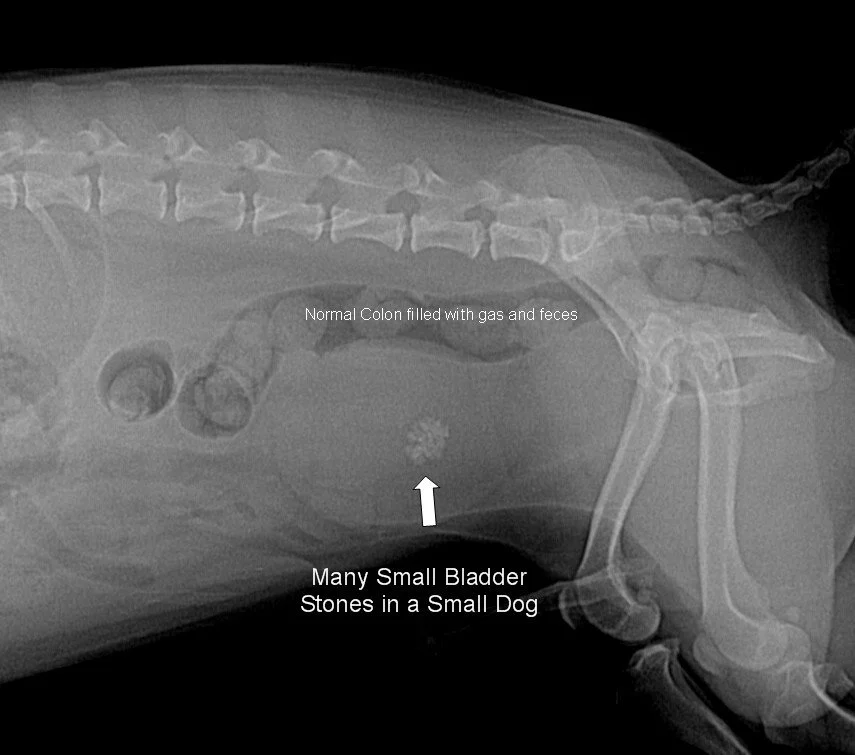

Examples